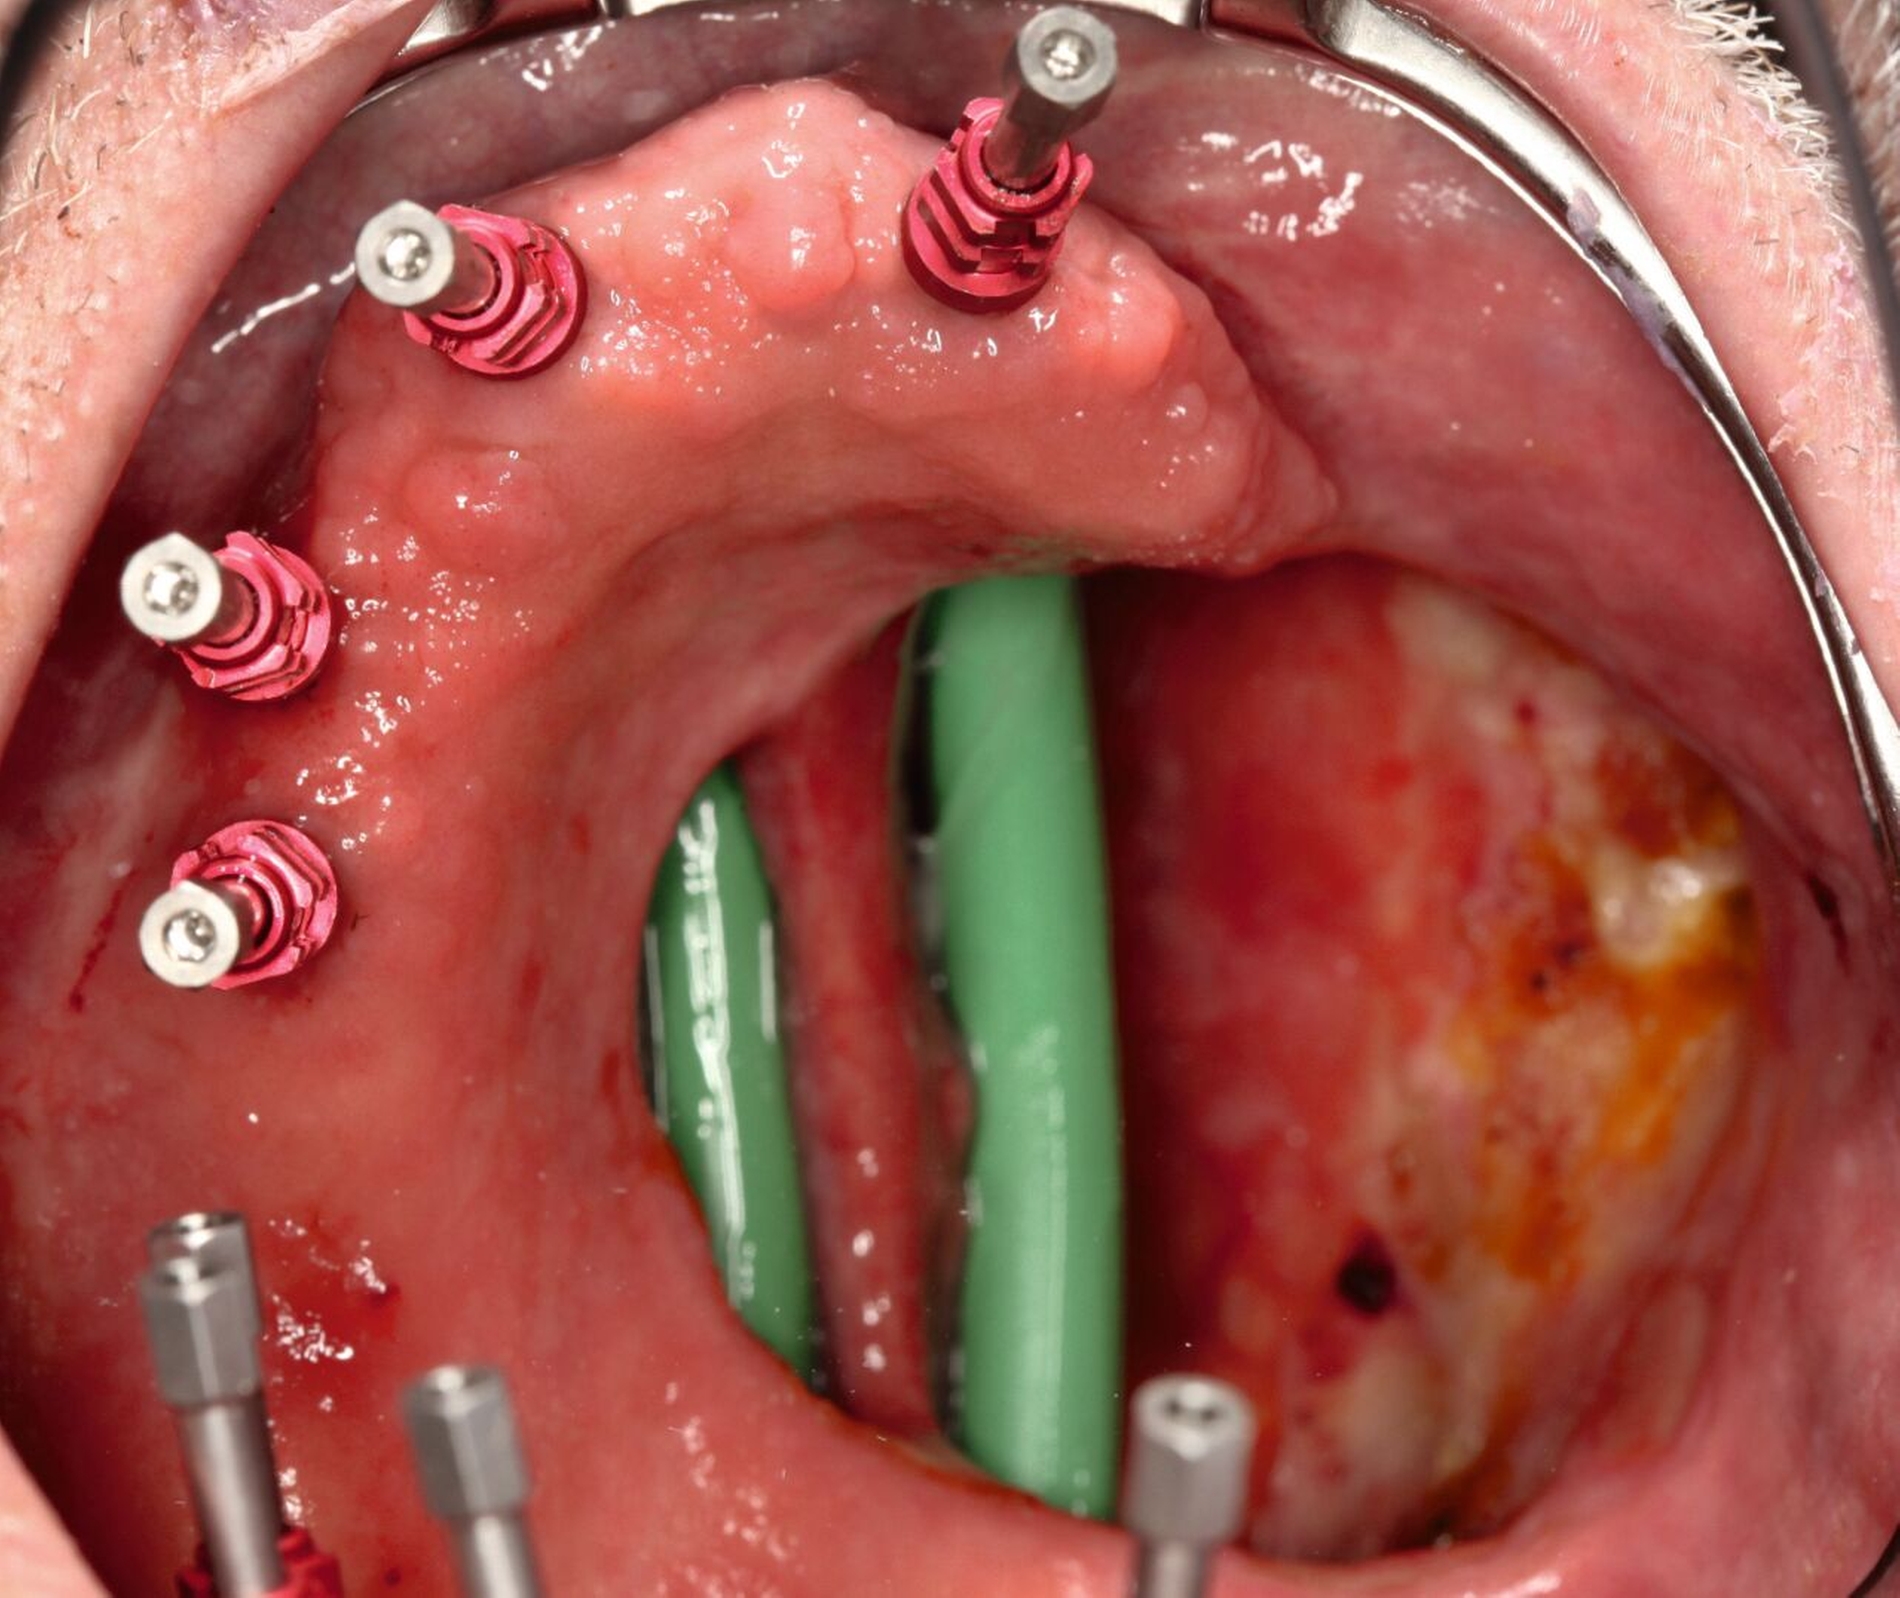

Mit Einbringen eines Wendel-Tubus zur Sicherung der Atemwege, lässt sich der Defekt ohne Probleme abformen (Abbildung 3). Jener verhindert auch, dass der spätere Silikon-Obturator die Atemwege nicht verlegt. Speziell visköses Silikon-Abformmaterial („Laborsilikon Orange“, 12 Shore A, Institut für Anaplastologie Schilling, Würzburg, Deutschland) verhindert ebenfalls, dass die Abformmasse in Richtung des Pharynx fließt. Nach der Defektabformung können die herkömmlichen Arbeitsschritte für einen Zahnersatz (als Zusatz zum Silikon-Obturator oder zur Herstellung einer Obturator-Prothese) erfolgen.